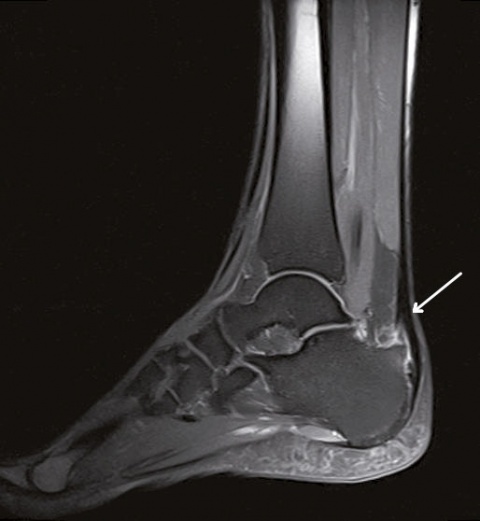

Die Persistenz der Beschwerden machte eine Vorstellung beim Facharzt für Orthopädie notwendig, der sonographisch eine Bursitis calcarea sowie eine Tendinitis der Achillessehne bei prominenter Haglundexostose diagnostizierte. Das in der weiteren Diagnostik durchgeführte Kernspintomogramm (MRT) zeigte zusätzlich eine Signalanhebung der präachillären Weichteile sowie ein zentrales Knochenmarködem im distalen Ansatzbereich des Kalkaneus.

bestehende Schmerzhaftigkeit der rechten Ferse, hier vor allem im Bereich 2 – 3 cm proximal des Ansatzes der Achillessehne am Kalkaneus. Eine erneute Bildgebung zur Kontrolle des Therapieerfolges mittels MRT zeigte hier weiterhin das Bild einer Tendinopathie bei Haglund-Exostose. Deshalb erfolgte eine intensive Beratung des Patienten hinsichtlich einer Operation nach Abschluss der immunmodulierenden Therapie, wofür sich der Patient aufgrund des immer noch hohen Leidensdruckes entscheiden konnte.

Ein einfacher Test zur Abgrenzung von einer Ruptur der Sehne mit Hämatom, Schwellung und eventuellem Tasten einer Delle ist nach wie vor der Simmonds-Thompson-Test (Plantarflexion des Fußes durch Kompression der Wadenmuskulatur bei intakter Achillessehne). Wie in der Kasuistik beschrieben, erfolgt die weitere Diagnostik mittels Sonographie der Ferse zur Darstellung einer Verdickung, Hypervaskularisation oder Zunahme von echoarmen Arealen. Zudem sollte eine Röntgenuntersuchung durchgeführt werden, um eine mögliche Haglund-Exostose zu detektieren. Eine Kernspintomographie der betroffenen Ferse eignet sich sehr gut zur Darstellung sowohl von strukturellen Veränderungen der Achillessehne, als auch begleitender Entzündungszeichen (siehe Abbildung 3).

Abbildung 3: Radiologische Praxen Kempten-Oberallgäu Dres. Vogel, Träger, Asbeck